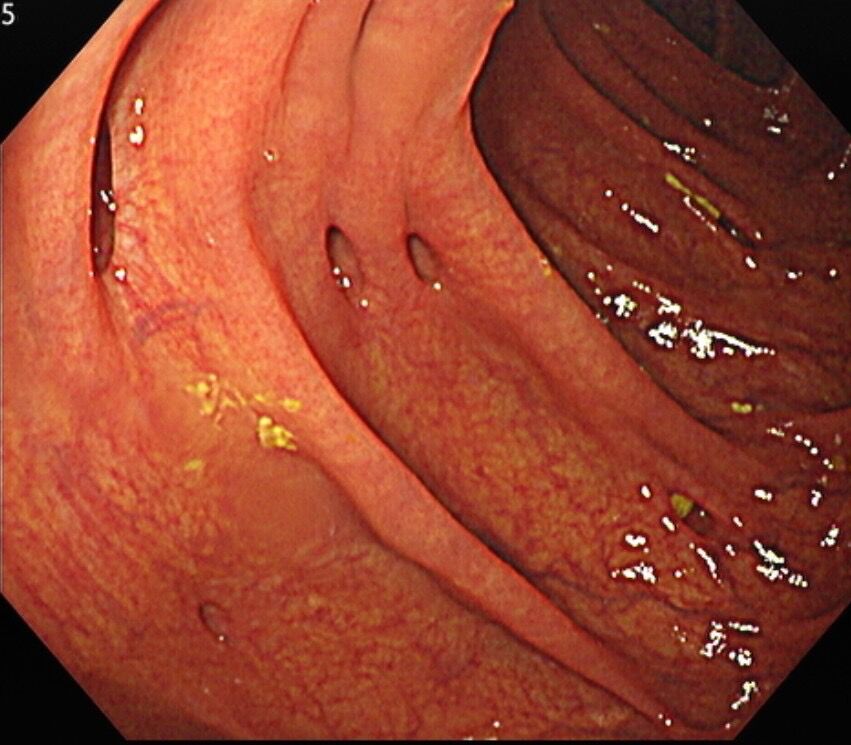

為什麼會有大腸憩室?你可以想像,就像年紀漸漸大了,皮膚的彈性會變差,50歲以後,大腸的肌肉層,也會變得比較脆弱、鬆弛。如果平常大腸用力收縮,企圖把糞便跟腸氣往下送時,就可能在大腸肌肉層結構較薄弱的位置,形成大腸憩室。所以做大腸鏡檢查時,腸壁看起來會像吹氣球一樣擠出一個個凹陷的「泡泡」,這就是大腸憩室。(編輯推薦:腸子有凹洞,發炎嚴重竟致穿孔阻塞!大腸憩室炎7個症狀別耽擱)

除了直腸外,大腸的盲腸、升結腸、橫結腸、降結腸、乙狀結腸,各個區段都可能長出憩室,但通常不是整條大腸都有憩室,而是集中在大腸的某一段,且位置不同,成因也有所差異。

- 左下腹(乙狀結腸): 多與老化及生活習慣有關。經常便秘、需要用力解便的族群,容易在乙狀結腸出現「成群結隊」的大腸憩室。

絕大多數的大腸憩室,並不會造成困擾,可以和平共存,往往是在做大腸鏡檢查時,意外被發現,若無症狀也不需要特別治療。不過,若大腸憩室反覆發炎或流血,導致腹痛、貧血或生活品質下降,醫師就會評估是否需要手術,把憩室集中的那一段大腸切除,避免問題一再復發。